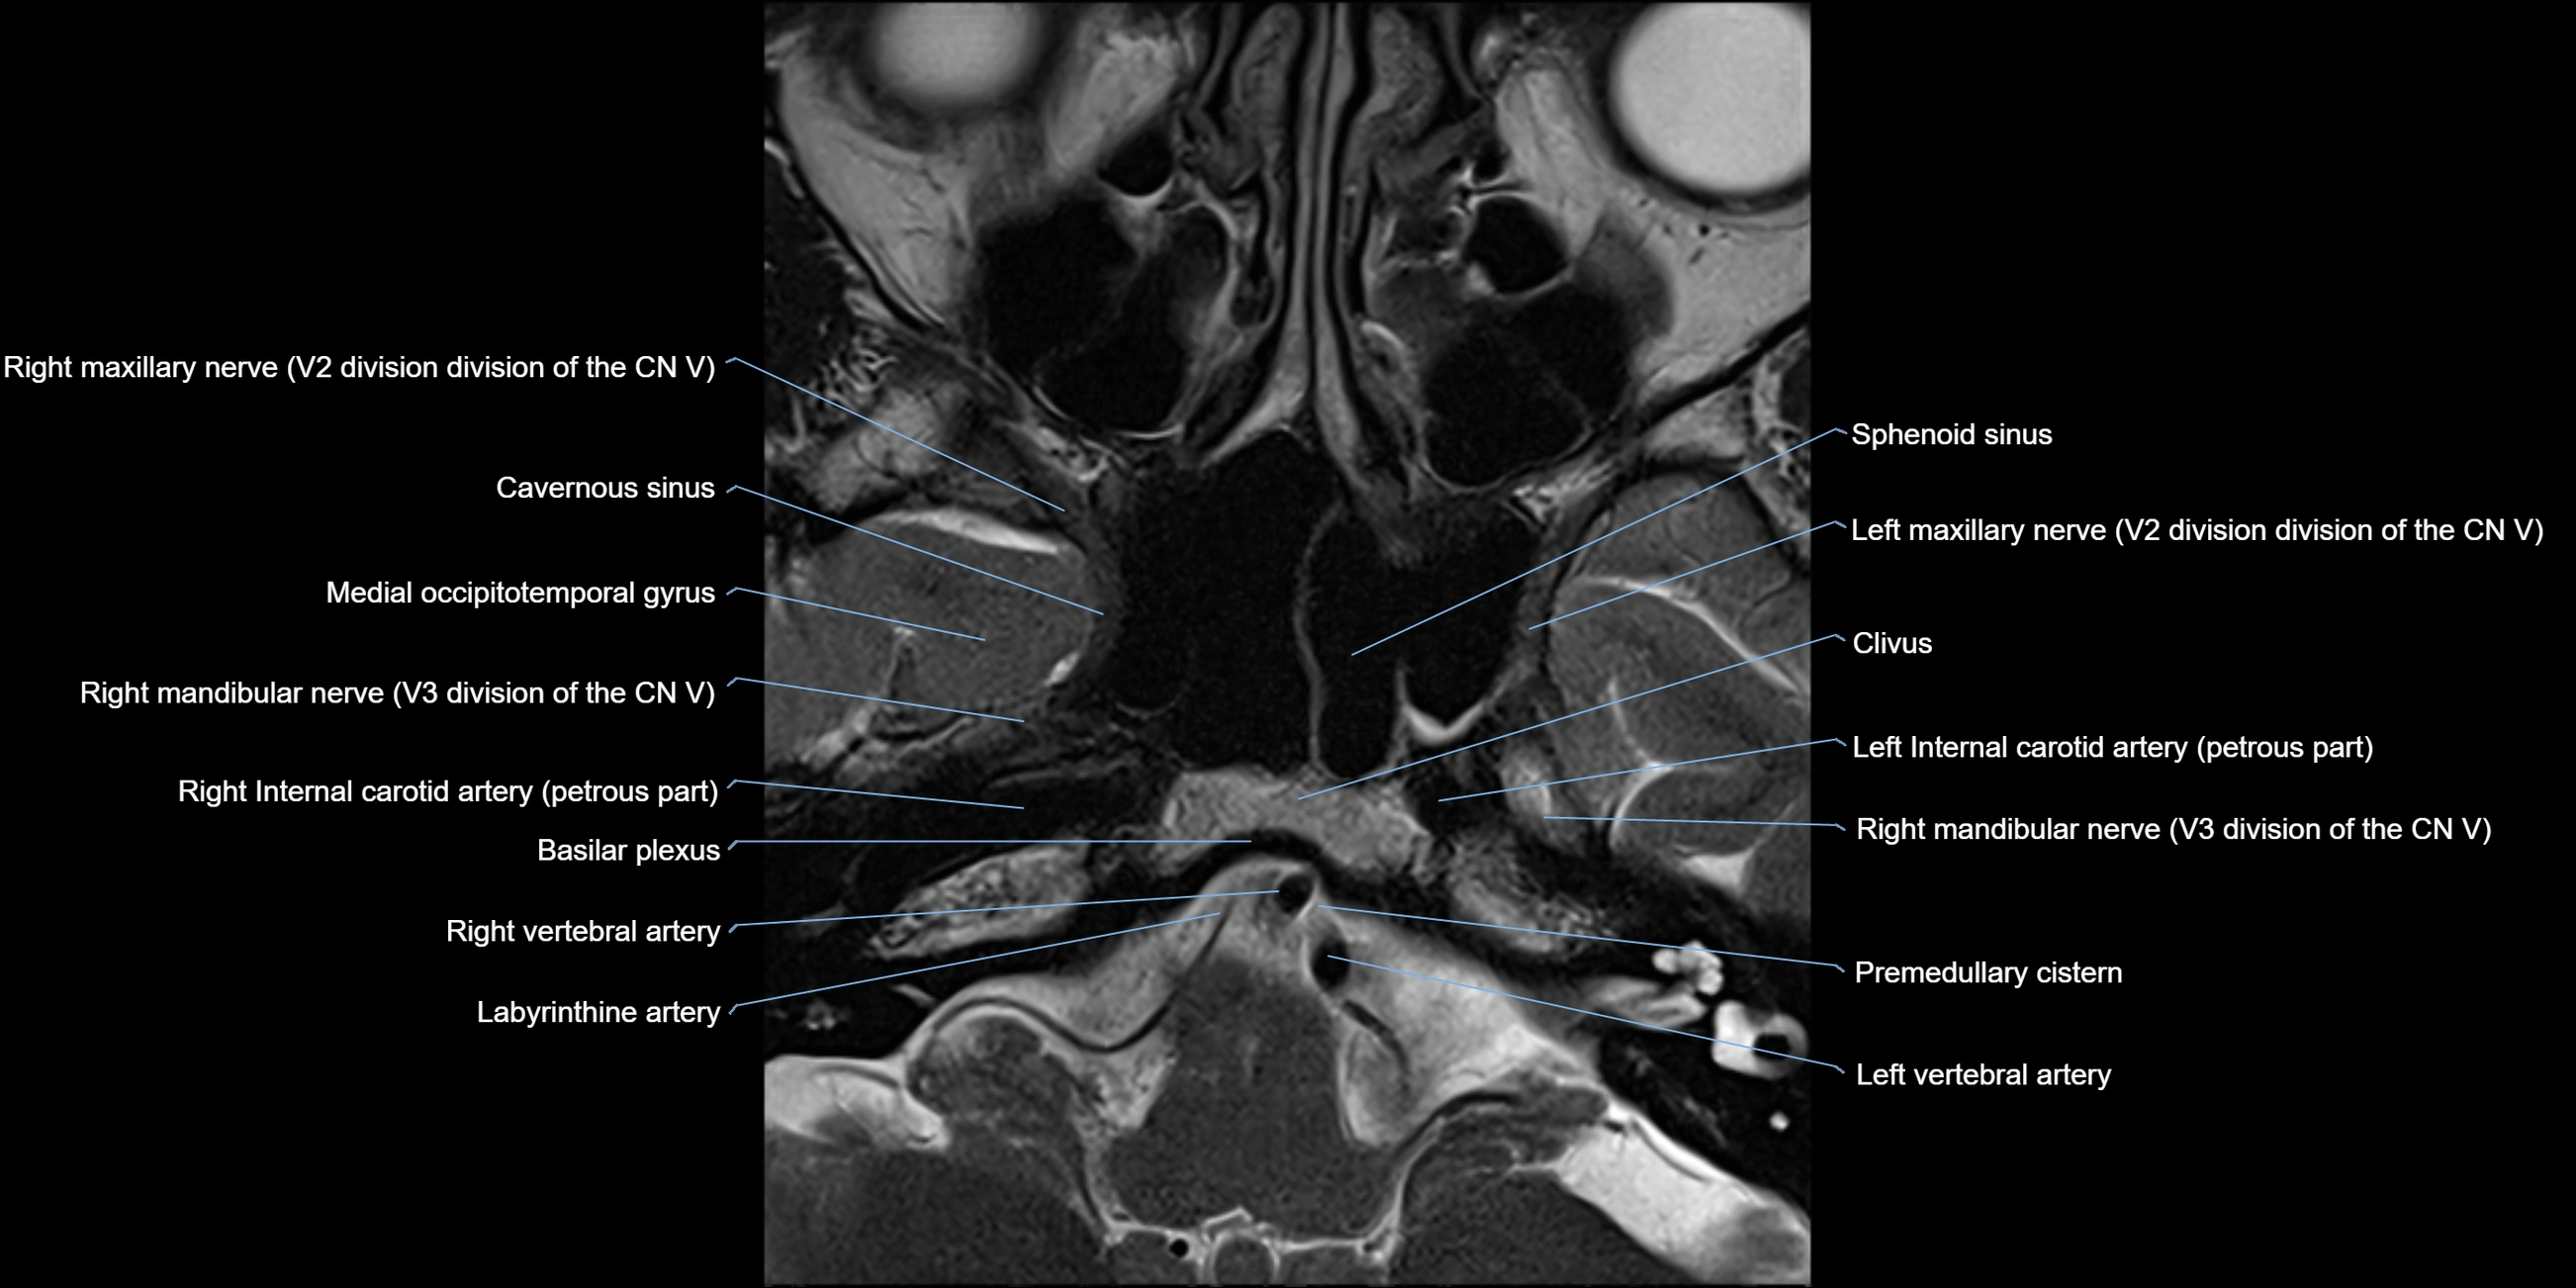

MRI Appearance

The abducens nerve is a small, thin, linear structure

Best visualized on high-resolution T2-weighted 3D MRI sequences (e.g., FIESTA or CISS)

Seen as a hypointense (dark) line running from the brainstem at the pontomedullary junction, traversing the prepontine cistern, and entering Dorello’s canal under the petrosphenoidal ligament, then into the cavernous sinus, and finally the orbit

May be challenging to visualize in standard MRI due to its small size

Pathology may be inferred by absence, displacement, or enhancement of the nerve

MRI images